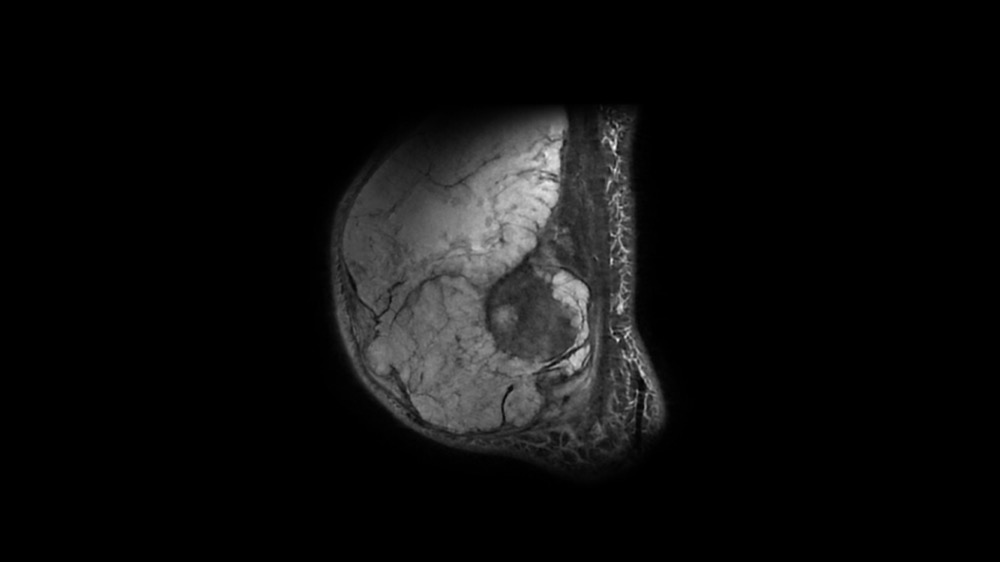

Bone Club

Bernard Hollier 18/05/2022